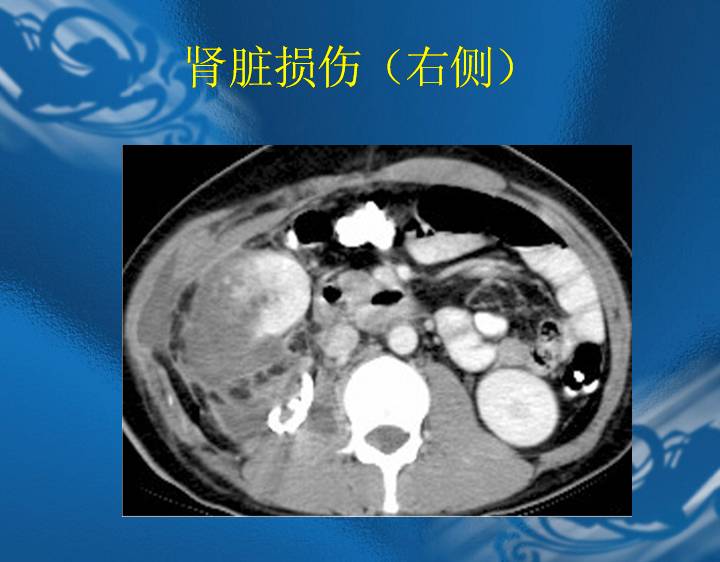

执业医师资格考试“实践技能”影像学辅导资料